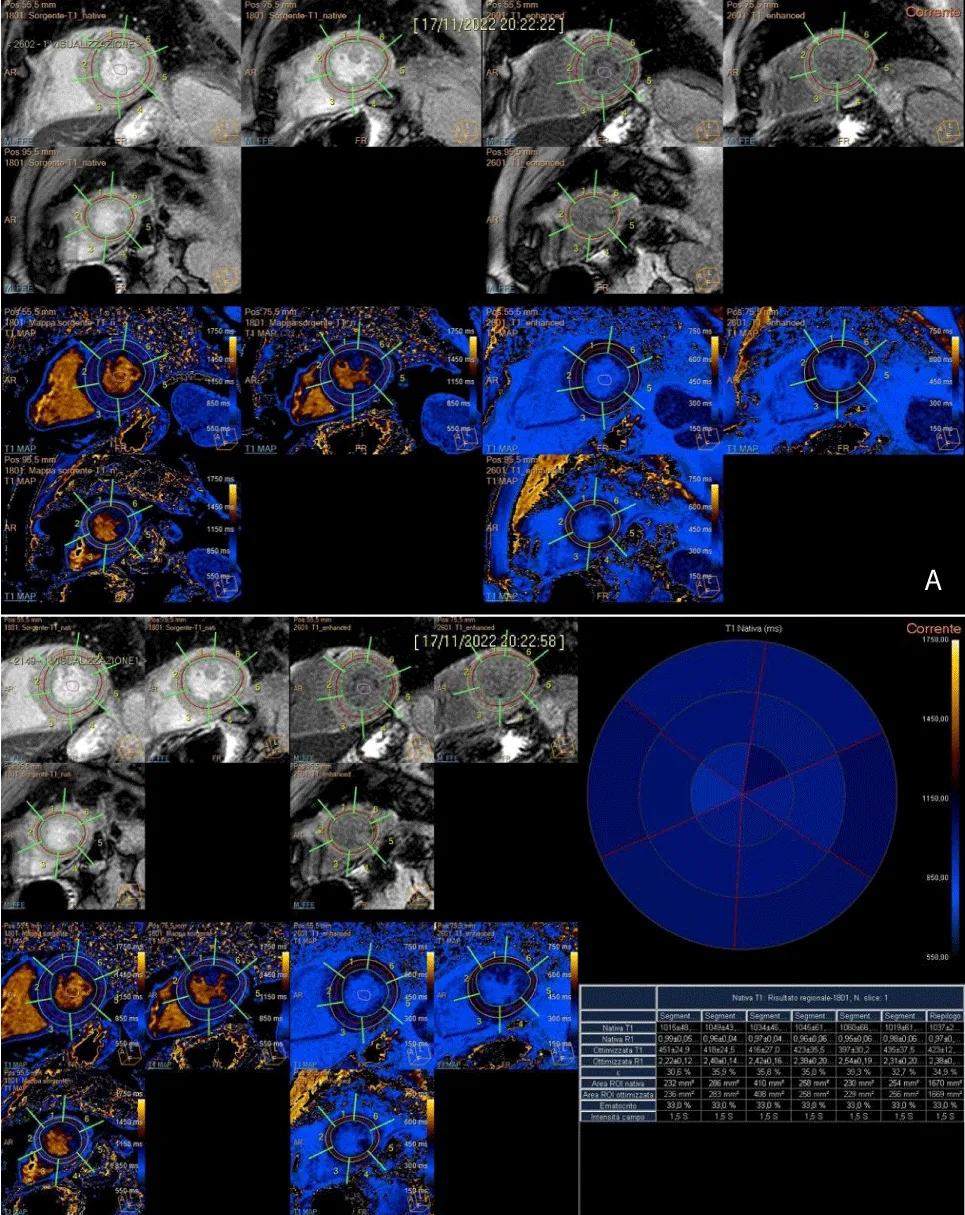

In the subsequent segmentation and results phases, the value by segment and average value for a section are extrapolated along 3 main plans acquired. In the re-elaboration of T1 in the segmentation phase, the hematocrit values are extrapolated from the laboratory parameters of the sampling carried out on the morning of the day of the survey. The addition of the hematocrit values is essential to extrapolate the ECV values, evaluated as both segment value and average value by section (Figure 4A and 4B).

Download Image

Figure 4: A). Post-processing T1 mapping, with the tracing of sub-endocardial and sub-epicardial borders, along three short-axial planes (basal, middle, and apical) and demarcation of intraluminal ROI. B). Semi-automatic quantitative analysis of T1 native, T1 enhanced with extrapolation of ECV.